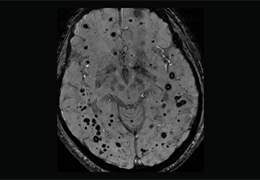

Eclipse 成像智能功能提供强大的处理能力和最佳质量的影像,同时减少质量错误并提高剂量效率。

凭借 AI、专有算法和先进的影像处理能力,提供出色的影像质量和无与伦比的诊断信心。

与标准影像处理相比,智能降噪功能可使客户降低辐射剂量,而不会损失影像质量。这在新生儿和儿科成像中尤其重要,在这种情况下以尽可能低的剂量成像至关重要。